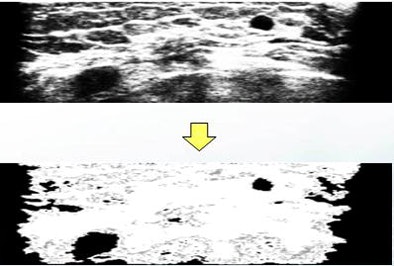

"Images are preprocessed by removing black regions, subsampling to reduce the detection time, and sigmoid filtering to enhance the boundary between tumor and normal tissue," Chang said. "A 3D fuzzy technique is adopted to detect tumor regions in the breast."

| Images are preprocessed by removing black regions, subsampling to reduce detection time, and sigmoid filtering to enhance the boundary between tumor and normal tissue. |

Each voxel is classified into one of three categories: tumor, boundary, and normal tissue, according to the intensity and edge information of the image, Chang explained. Regions classified as tumor are not all tumors, he added. Some are darker regions representing acoustic shadowing or nipple regions.

The results of fuzzy reasoning show tumor regions in black, boundary regions in gray, and normal tissue in white.